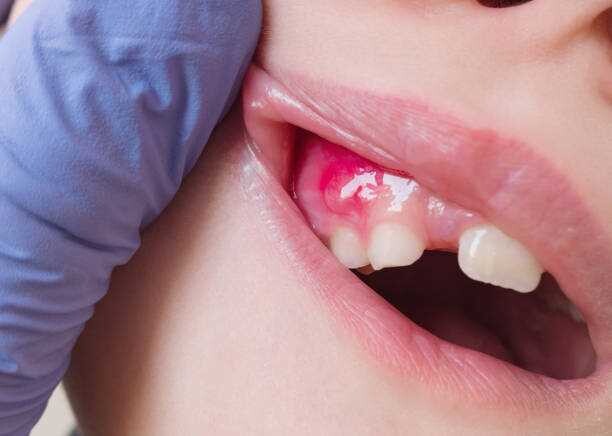

What Is A Tooth Abscess?

A tooth abscess is a bacterial infection found in the inner part of the tooth where pus has collected and can cause moderate to severe pain in people who suffer from the condition. Tooth abscesses can occur when a cavity has gone untreated for too long or when a crack or chip in the tooth allows bacteria to find its way into the dental pulp (the inner, soft part of the tooth) area of the tooth and gets infected.

Once the bacteria has made its way inside, it will spread down to the root and cause both inflammation and swelling. Once inflammation occurs, it will force the pus into a tight space (known as the abscess) at the tip of the root where the swelling exists.

Symptoms

Signs and symptoms of a tooth abscess include:

Persistent, throbbing or severe toothache

Extreme temperature sensitivity

Pain when performing normal chewing or biting

Fever

Swelling in the face or the cheeks

Lymph nodes under the jaw or in the neck become tender or swollen

A rush of foul-tasting fluid in the mouth followed by cessation of pain, which means the abscess has ruptured